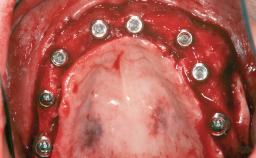

# of Teeth 14

# of Implants 12

Type of Implants One-Piece|Reduced-Diameter